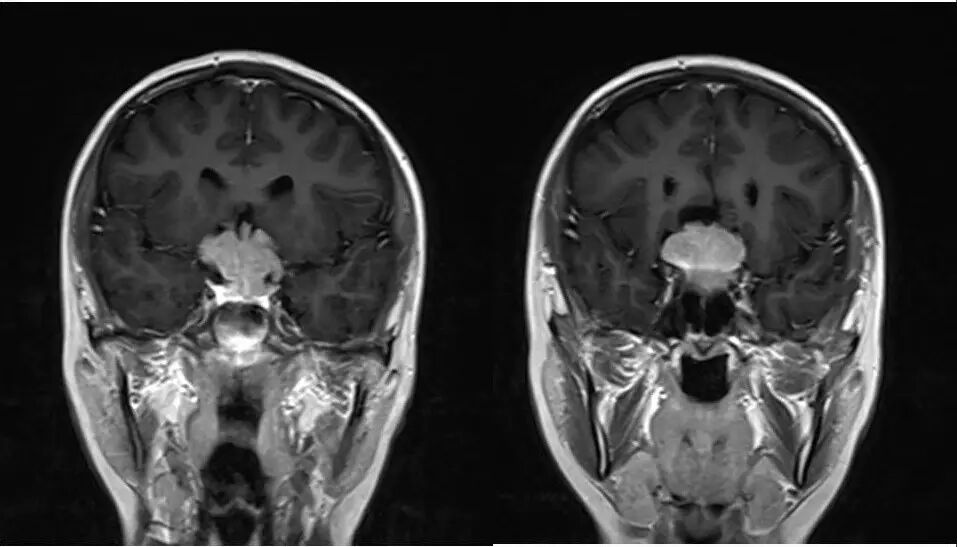

4.重点观察冠状位:病变源于垂体偏左侧,与垂体界限不清楚,肿瘤偏右侧可见垂体与肿瘤之间裂隙,造成矢状位平扫及强化后误认为正常垂体存在,从而首先除外了垂体瘤,导致误诊;

5.影像表现确定肿瘤源于垂体,部位、信号、生长方式、内部结构、骨质破坏,增强显示等均符合垂体瘤诊断。